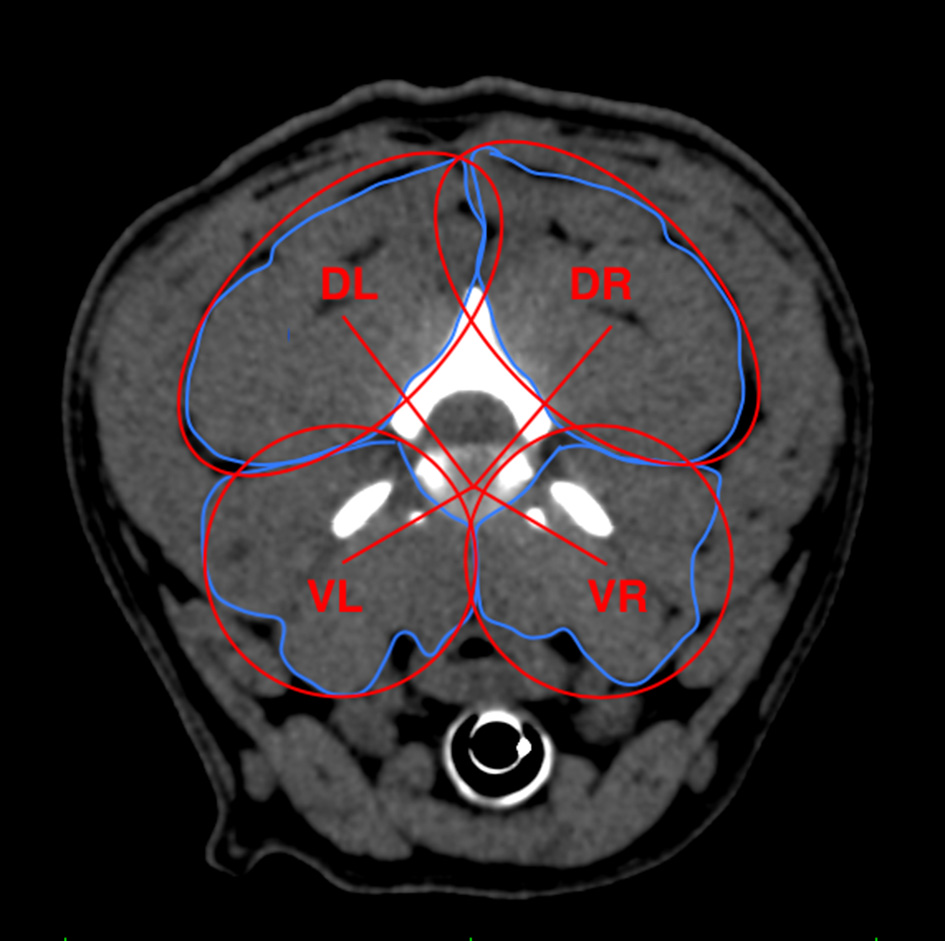

Ratio of Moments

The ratio of moments was calculated to determine the forces affecting the vertebral body and to compare the dorsal and ventral load. Four ellipses were placed over the vr, vl, dr, and dl muscle groups to measure the area ratio. To calculate the ratio of moments, the center of the assumptive muscle group was identified with the ellipsoid models. The distances from the muscle group centers to the disk center at each level of the cervical spinal cord were measured, describing the lever arms of each of the four muscle groups (VR = ventral right, VL = ventral left, DR = dorsal right, DL = dorsal left) (Figure 5). Finally, the relation between the four moments was defined by the equation described by Hartmann et al. (1). Mean ratio of moments was calculated for both FB groups to determine statistically significant differences.

Figure 5

Measurement scheme describing the distances between the disk center and assumptive center of the muscle groups calculated with ellipsoid models to further determine respective relation of moments. Red lines describing lever arms of each paraspinal muscle group. DR, dorsal right; DL, dorsal left; VR, ventral right; VL, ventral left.